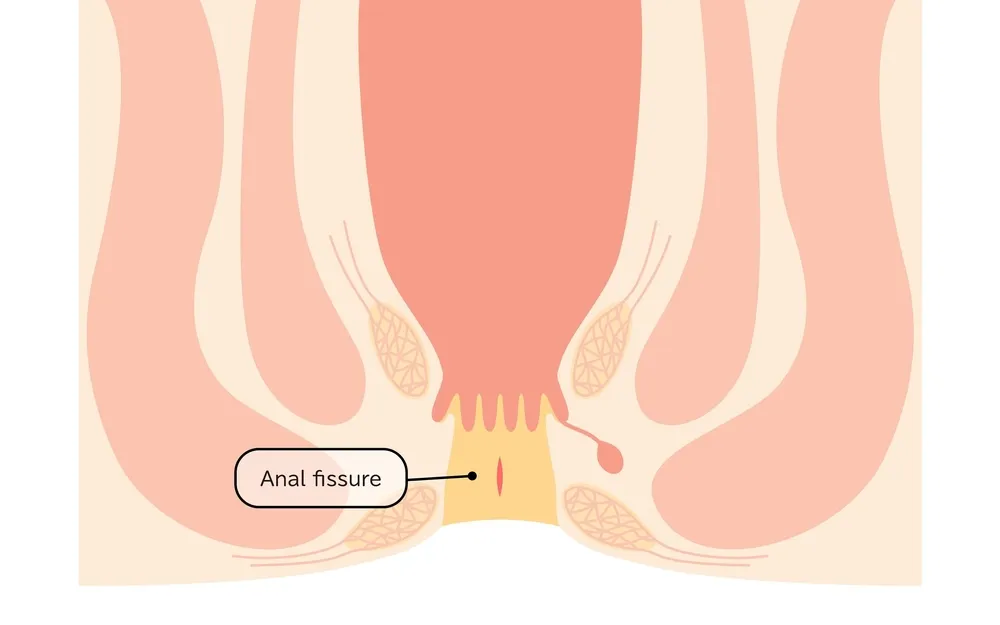

۲. شقاق یا فیشر مقعدی

شقاق به معنای ایجاد ترک یا زخم در دیواره کانال مقعدی است که معمولاً در اثر یبوست مزمن، دفع مدفوع سفت یا تحریکات مداوم به وجود میآید. درد شدید در هنگام دفع و خونریزی از علائم مشخص آن است.

همه چیز درباره شقاق یا ترک مقعدی و راهکارهای درمانی آن

شقاق مقعدی یا فیشر آنال (Anal Fissure) یکی از شایعترین و دردناکترین بیماریهای ناحیه نشیمنگاهی است که بهصورت یک پارگی یا ترک طولی در دیواره داخلی کانال مقعدی ظاهر میشود. این آسیب اغلب در لایه پوششی مخاطی ناحیه انتهایی کانال آنال ایجاد میشود و میتواند با علائمی همچون درد سوزاننده، خونریزی، و اسپاسم عضلانی همراه باشد. گرچه شقاق در بیشتر موارد بدون مداخله جراحی و با درمانهای محافظهکارانه بهبود مییابد، اما در برخی بیماران ممکن است مزمن شده و نیاز به مداخلات تخصصیتر داشته باشد.

آناتومی و ناحیه درگیر در شقاق مقعدی

شقاق معمولاً در دیواره خلفی کانال آنال و در خط وسط ایجاد میشود؛ جایی که خونرسانی نسبتاً کمتر است و فشار در زمان دفع بالاتر میرود. در موارد نادر، شقاق ممکن است در قسمت قدامی یا در هر دو سمت همزمان دیده شود، بهویژه در بیمارانی که دچار بیماریهای زمینهای مانند کرون یا زخمهای ایمنی هستند. عمق ترک بسته به شدت آسیب، از یک خراش سطحی تا زخم عمیق با نمای بافت فیبروزه و پولیپ نگهبان متغیر است.

علائم شقاق یا فیشر مقعدی

علائم بالینی این بیماری معمولاً بسیار مشخص و آزاردهندهاند و شامل موارد زیر میشوند:

درد شدید و برنده در هنگام دفع مدفوع که ممکن است چندین دقیقه تا چند ساعت پس از دفع ادامه یابد.

خونریزی روشن بهصورت رگهای روی مدفوع یا قطراتی در توالت.

در نوع مزمن، ممکن است زائدهای در لبه مقعد (بهنام «پولیپ نگهبان») ظاهر شود که نشانهای از طولانیبودن روند بیماری است.